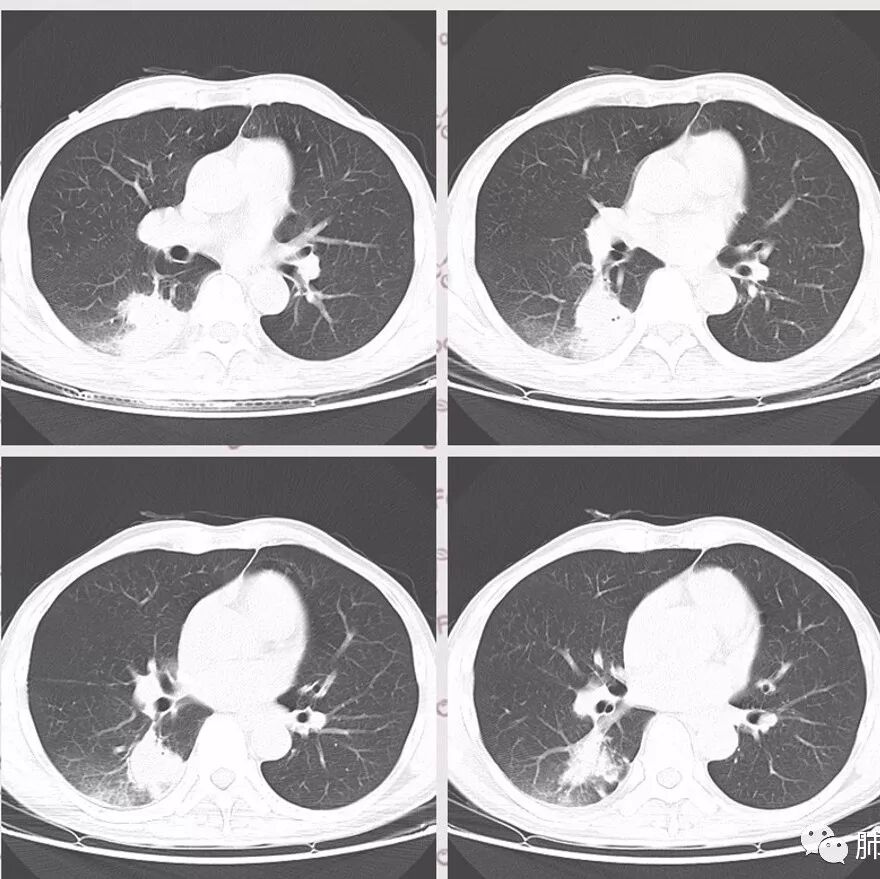

胸部CT:右肺下叶背段实变,广基底,糊墙,长轴与胸膜平行,周围晕,支气管进入堵塞,纵隔窗可见低密度坏死,实变内小空洞?脑部不会看。

胸CT:右肺下叶背段实变影,内可见小空泡,病灶与胸膜呈宽基底,实变病灶周围存在毛玻璃影,纵隔窗可见病灶内存在低密度,增强可见病灶强化,并见病灶内低密度区。头MRI不会看。

右肺下叶背段实变,广基底,糊墙,长轴与平行胸膜,周围有晕,支气管进入堵塞,可见低密度坏死及小空泡。颅内多发环形强化灶,符合脑脓肿三层结构,结合临床,考虑:感染性病变,隐球菌?鉴别肺克。

蔡磊:

肺部病灶有收缩性,支持感染性病变,但是患者病程不急,不支持肺克

右肺下叶大片实变

我们回头看肺内的,病灶位于下叶背段,可惜没重建

近肺门区见一坏死腔,内壁较清楚,空泡在周围

单从这个坏死我们分析:1、炎性?2、鳞癌?

厚薄均匀,强化一致,未见壁结节,坏死位于病灶近端,我会首先考虑炎性

局部部分边缘膨隆,欠光滑

不是单纯的近端堵塞,远端不张,远端实变,宽基底

远端实变区膨隆,部分似有栽赃的趋势

感染一定有,但是应该还有警惕癌

2.影像右肺下叶大片高密度影,整体边界模糊柔和,中央见圆形液化区及微小气泡影,内壁相当光整,环形强化,未见明确壁结节。双肺门及纵隔未见增大淋巴结。这样的病灶更符合细菌性肺脓肿,以肺炎克雷伯杆菌感染最为常见。